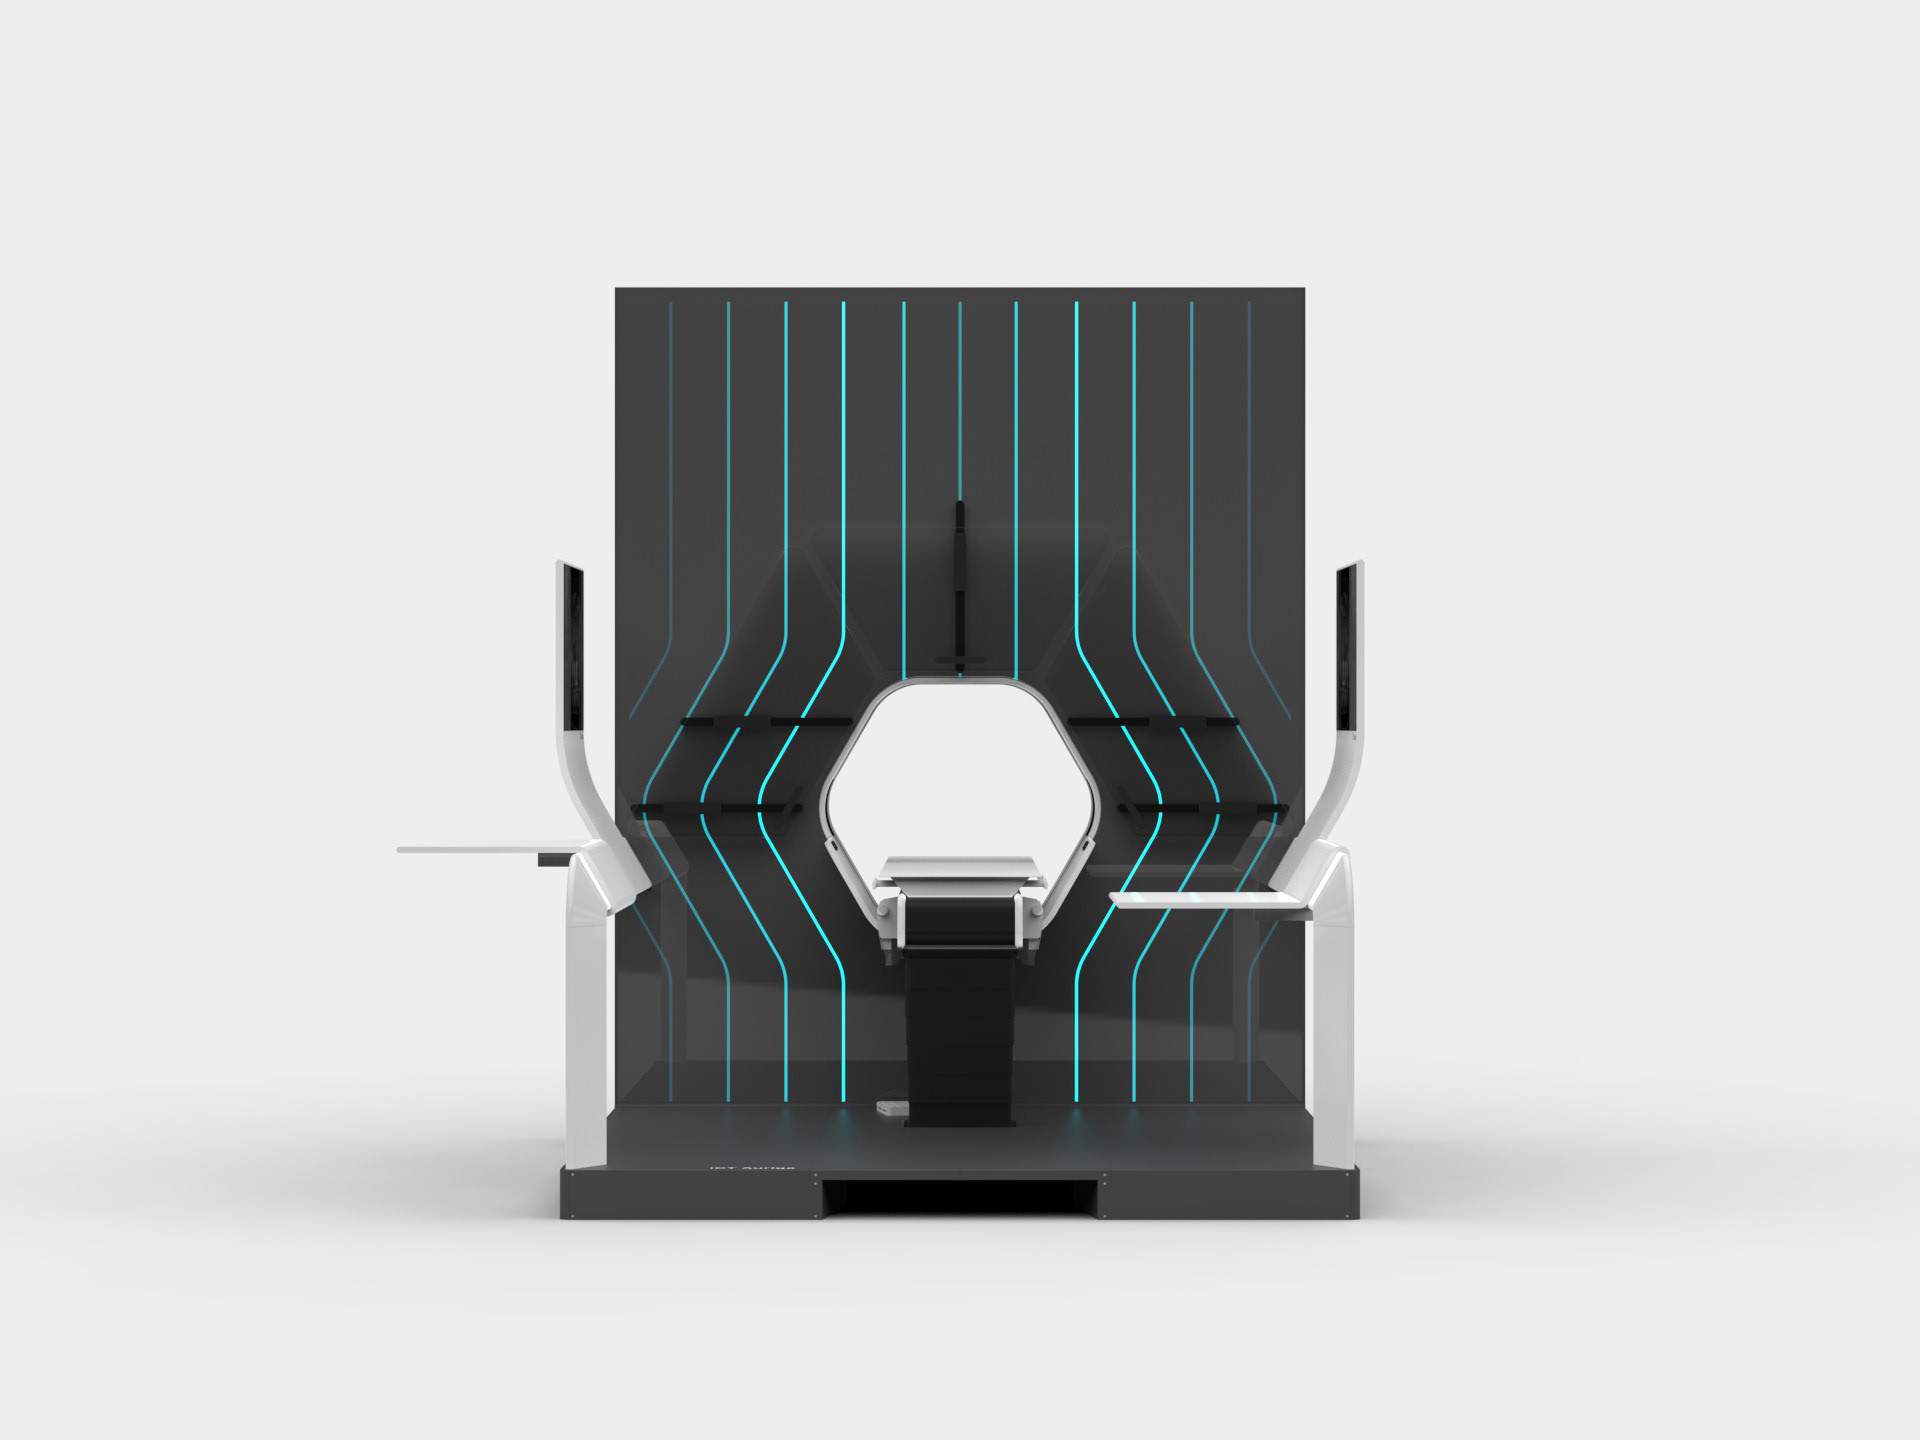

Auriga is an architecturally inspired CT device. The gantry extends to the ceiling and becomes a spatial installation. This takes away its massive “machine-character” and makes it part of the room. The gantry height is individually adapted to the given space - individuality becomes part of the product. In order to enable right- and left-handed working, the overall construction is symmetrical and intervention from both sides is equally possible.

The central design feature is the hexagonal gantry opening. It provides space for the lamps and displays. The large fronts of the gantry offer space for a display of different coloured patterns and animations, which visualize the radiation. These can be individually selected and adapted together with the overall height of the gantry. The patterns pick up on the hexagonal shape of the gantry opening and set it off. To protect the interventionists from radiation, lead glass panels and a radiation protection tray are installed. The sliding lead glass panels allow individual adaptation to the patient and the interventionists working space. The tray serves to protect the abdomen and offers a lot of foot space as well as a front leaning aid for a safe stand.

DESIGN